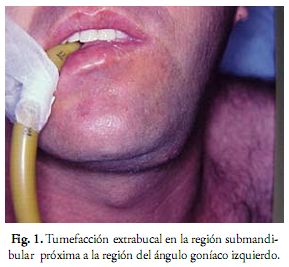

Paciente de sexo masculino, de 30 años, consulta por la presencia de una tumefacción en la región submandibular izquierda, próxima a la región del ángulo goníaco (Fig. 1). Al examen clínico se observa una lesión de consistencia firme, sin movilidad, indolora, con coloración normal de piel y mucosa y sin afectación de ganglios linfáticos. El paciente relata dos años de evolución y un crecimiento lento del nódulo y no refiere antecedentes de trauma en la región. Es un practicante de deportes y agricultor, lo que puede sugerir situaciones remotas de traumatismos en la cara. Otro hallazgo clínico a destacar fue la presencia de mordida cruzada en el lado posterior izquierdo.